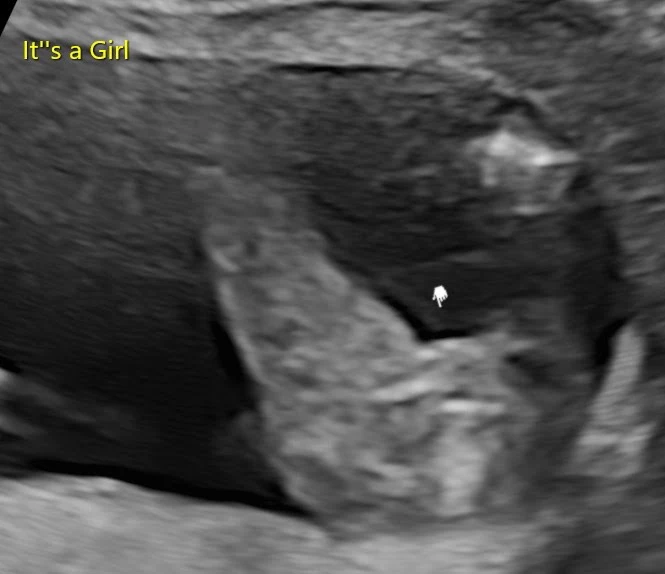

토리의 성별을 확인하다

IMG_9299.JPG Baby Girl!

임신 16주쯤부터는 성별 확인을 할 수 있다. 나는 20주 스캔까지 기다릴 수 없어서 또(!) 프라이빗 스캔을 다녀왔다. 영국에서는 젠더 리빌 파티 (Gender Reveal Party)라고, 아이의 성별을 확인하는 파티를 하는 경우가 많은데 그래서인지 이 스캔 센터에서는 예약할 때 '성별을 너에게 알려줄까, 아니면 따로 써서 줄까'라고 물어본다. 만약 파티를 생각하고 있다면 따로 종이에 성별을 써주고 그걸 파티 주최자 (보통 가장 친한 친구)에게 주면 그에 맞게 파티를 준비하는 것.

토리는 Baby Girl, 딸이었다.